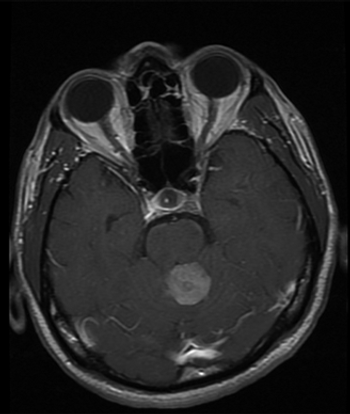

MGMT Methylation a Survival Biomarker in High-Risk Low-Grade Gliomas?

These are the first data to highlight the prognostic value of MGMT methylation beyond the IDH1/2 mutation status test currently used to help predict glioma patient survival outcomes.